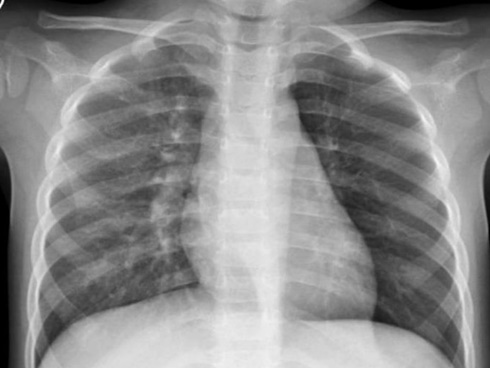

Phát hiện các triệu chứng nghi ngờ của viêm đường hô hấp